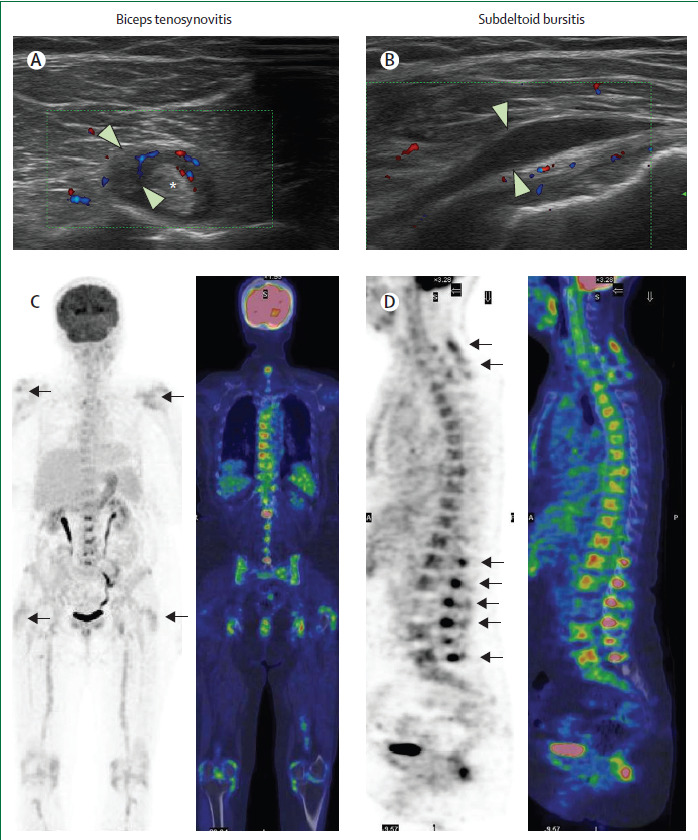

超音波検査やMRI検査によると、両側の軽度の肩峰下滑液包炎や三角筋下滑液包炎は、リウマチ性多発筋痛症の32~93%にみられる。さらに、肩関節包炎(69%)、腱板腱炎(72%)、上腕二頭筋腱鞘炎(37〜60%)は、未治療のリウマチ性多発筋痛症患者によくみられる所見である

PETでは、肩、胸鎖関節、臀部、坐骨結節、臀部に ¹⁸FDGの取り込みが認められる。リウマチ性多発筋痛症のもう1つの特徴的な病変は、頸椎および腰椎の棘突起間滑液包炎であり、患者の約50%で超音波、MRI、または¹⁸FDG-PETを用いて観察される(図2)